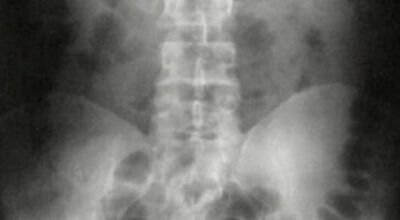

Esta recopilación de imágenes recoge alguna de las situaciones más estrambóticas que se han podido dar en una sala de rayos X. Todas ellas tienen algo en común: Son objetos extraños para el cuerpo humano que, de alguna manera han encontrado una vía de entrada, pero se han perdido a la hora de encontrar la de salida.

Muñecas de juguete descabezadas, botellas, armas, frascos, botes de plástico, teléfonos y hasta una cinta de casete pueden encontrarse en esa suerte de “punto limpio” al que ha quedado reducido el interior de los afectados.

No sabemos, ni juzgamos, la forma o los motivos por los que terminaron atrapados en dichas partes del cuerpo, pero estamos convencidos de que algún doctor estuvo al borde de la carcajada cuando se encontró con casos tan llamativos e inverosímiles como estos ¡Ver para creer!